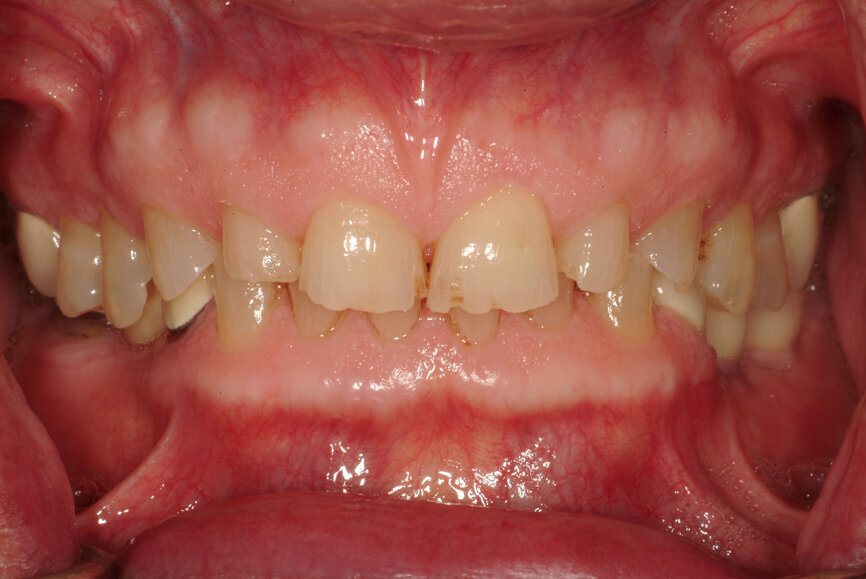

Fig. 13: Intercuspation requiring opening of the vertical dimension for restorative space.

- To obtain restorative space when needed restorations require an opening of the vertical dimension (Fig. 13);[21, 22]